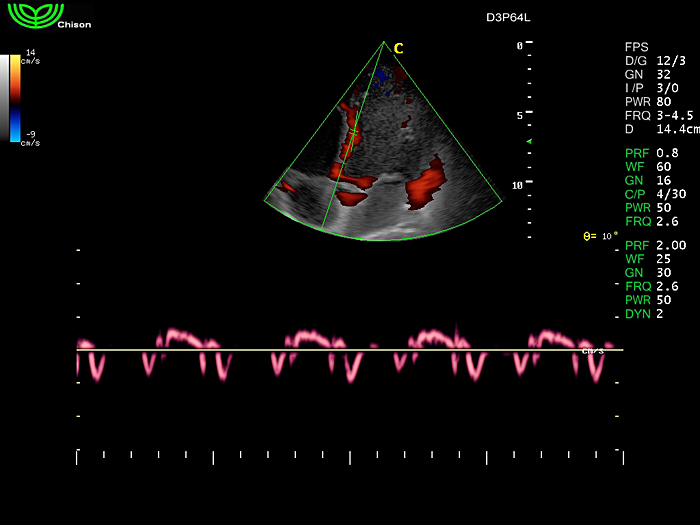

D3P64L 3.0МГц, фазированная решетка.

2.0МГц – 4.4МГц. Применения: кардиология, брюшная полость, акушерство. |